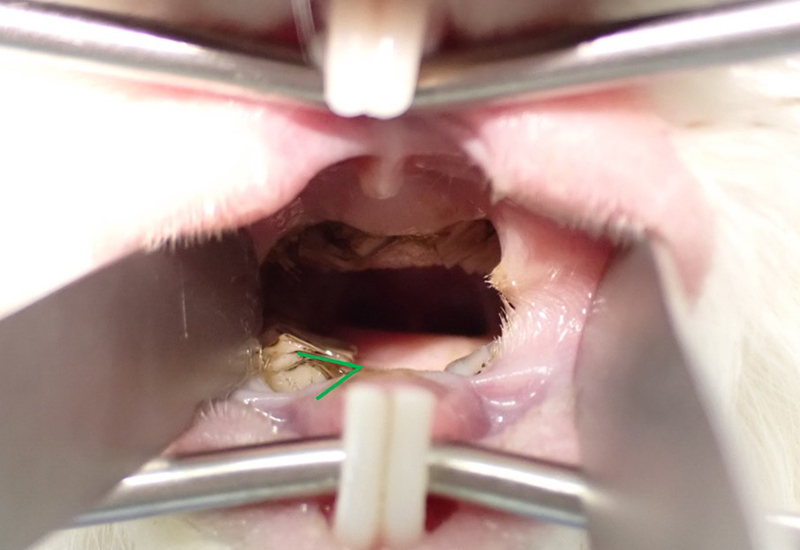

Cavidad bucal de la cobaya antes del tratamientoComo se puede observar, la muela derecha (indicada por el marcador verde) se superpone ligeramente a la lengua.

En los humanos, podemos comer incluso si nuestros dientes se superponen ligeramente a la lengua, pero en los conejillos de indias, los dos tercios posteriores de la lengua son fijos y solo la punta puede moverse. Debido a esta estructura única, si los dientes crecen demasiado, como se muestra en la imagen superior, el movimiento de la lengua hacia la izquierda, la derecha, arriba y abajo se ve obstaculizado, lo que imposibilita que el alimento llegue a la parte posterior de la garganta.